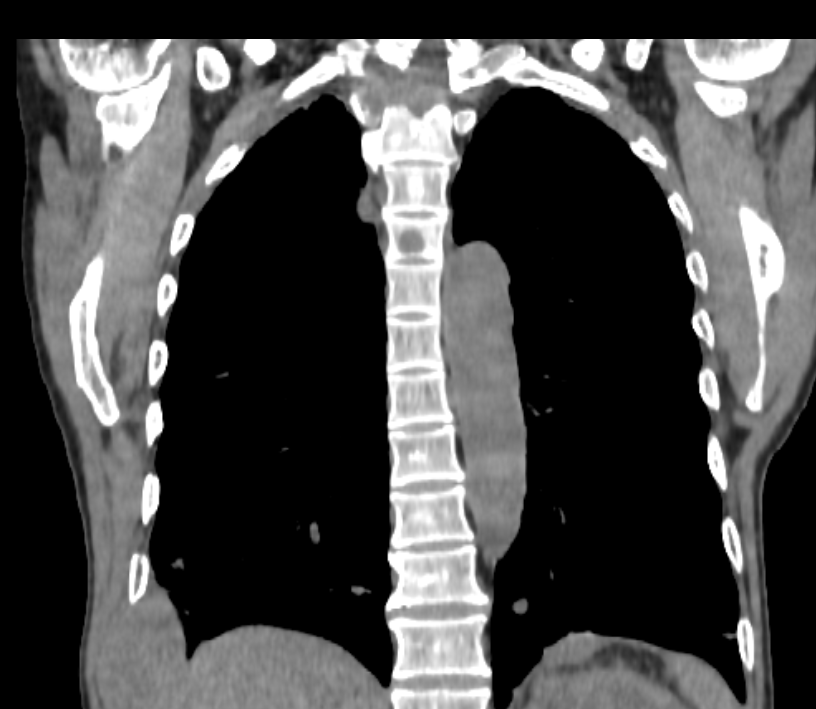

A heterogeneously enhancing soft tissue mass lesion centred on the right posterolateral 9th rib, measuring 6.8 x 3.7 cm in greatest transaxial dimensions, with associated underlying rib destruction is seen.

An enhancing soft tissue mass lesion centred on the left posterior 5th rib, measuring 2.7 x 1.2 cm in greatest transaxial dimensions, with associated underlying rib destruction is seen.

A hyperenhancing soft tissue mass lesion centred on the T1 vertebral body causing destruction of T1 vertebral body, right pedicle, right transverse process, posterior right first rib with extension of lesion in spinal canal leading to cord compression. Superiorly mass extent to right transverse process of C7 vertebra with bony destruction.Inferiorly lesion extent to anterolateral aspect of T2 vertebral body.

Another hyperenhancing soft tissue mass lesion measures 3.8 x 3.5 cm is seen in right paraspinal region at T3 & T4 vertebral level causing destruction of right pedicle and transverse process of T3 & T4 vertebrae. Posterior 3rd and 4th ribs destruction is also noted.

- Multiple varying size enhancing soft tissue nodules are seen in both lung fields.

- Mild paraseptal emphysematous changes are seen in both lungs upper lobe.